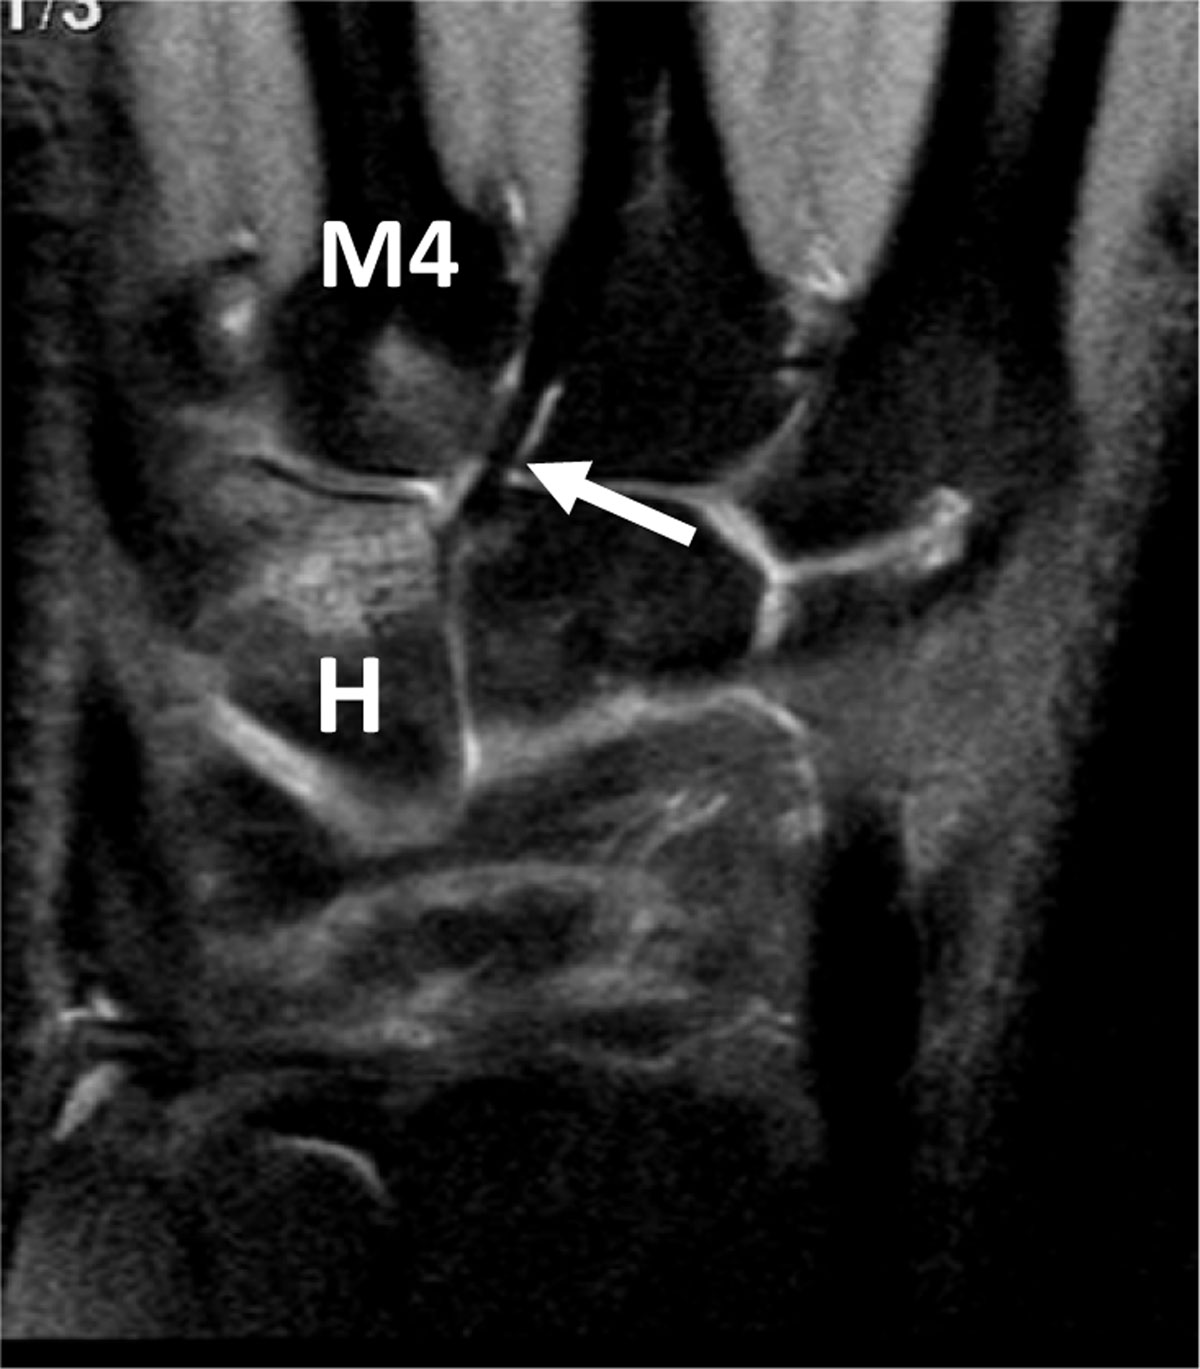

Figure 8

Hamate BME and associated BME of the fourth metacarpal base in an overused pianist hand. Coronal proton-density fat-saturated MR image depicts high signal bone marrow infiltration of the distal half of the hamatum (H) and proximal base of the fourth metacarpal (M4) nearby the capito-third metacarpal ligament (arrow) which is strong in this professional piano player.